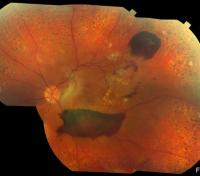

For millions of Americans, their world is dissolving into an unrecognizable blur. Diabetic retinopathy is an eye disease affecting one-third of the estimated 30 million Americans who struggle with diabetes. As the patients' vision slowly fades, it never recovers and few treatments are available.

Researchers at University of Utah Health have identified a protein (ARF6) that when inhibited reduces diabetic retinopathy, a condition that results when blood vessels at the back of the eye leak fluid into the eye, impairing vision. Published in the October 23 issue of The Journal of Clinical Investigation, these results offer an opportunity to develop new treatments for this eye disorder.

Studies were conducted in rodents treated to simulate the diabetic condition. By injecting NAV-2729 into the eyes of these animals, vessel leakage, as well as, the overgrowth of blood vessels, another driver of disease, were significantly reduced.

Today, patients with diabetic eye disease can receive monthly anti-VEGF injections directly into the eye to reduce inflammation, a treatment that is successful in only 40 percent of patients. In the study, injections of NAV-2729 into the eyes of diabetic mice were more effective in reducing blood vessel leakage than the anti-VEGF injections.

"Diabetic retinopathy can develop over time, leading to dramatic vision loss that may not be improved with glasses," said M. Elizabeth Hartnett, M.D., professor in Ophthalmology and Visual Sciences at Moran Eye Center and a contributor to this study. "New treatments are needed, because diabetic retinopathy is increasing world-wide and anticipated to increase more in the next decades."